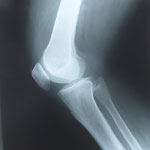

התערבות כירורגית במקום גבס, ניתוחים בעזרת מצלמה קטנה ועוד - כל מה שחדש בתחום כירורגיה של הכתף והמרפק תת-ההתמחות בכירורגיה של המרפק והכתף הינה תחום חדש יחסית בכירורגיה אורטופדית. ככל שהבנתנו את מנגנון הפעולה של מפרקים אלו משתפרת, כך גם משתפרת יכולתנו לטפל בבעיות הנובעות מהם. חבלות הנובעות מתאונות דרכים ותאונות עבודה גורמות לעתים קרובות לשברים בגפה העליונה. השימוש בגבס שהיה נפוץ בעבר בקיבוע מפרקי הכתף והמרפק כבר הפך לנחלת העבר היות והקיבוע יכול להביא לפגיעה קשה בטווח התנועה שלה. הדגש כיום הינו על הפעלת המפרק מוקדם ככל האפשר, לאחר התערבות כירורגית למניעת היווצרות קישיון של המפרק. בעיות בכתף ובמרפק יכולות לנבוע הן מהעצמות והן מגידים, ומשרירים ורצועות המקיפים אותם. ניתן לטפל בדלקת על-ידי טיפול פיזיותראפי, הזרקות קורטיזון מקומיות וטיפול תרופתי. כאשר נוצרים קרעים בקבוצת גידים זו, לעתים...